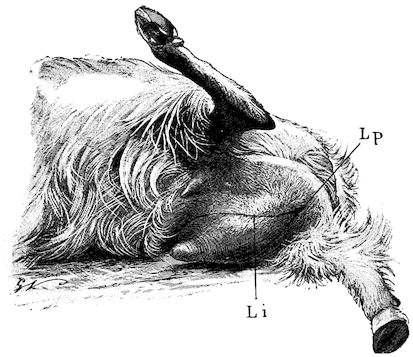

Fig. 2.—Horse suffering from osseous cachexia.

114. The fourth phase, or period of osteomalacia, i.e. softening of the bones, is also the last. It is rarely seen in large animals like horses and oxen, because accidents so often accompany the preceding stages and necessitate slaughter; but it is common in goats and pigs.

In the goat, the disease shows some slight peculiarities. Thus, in the second phase, during which goats and sheep suffer so markedly from lameness and pain in the bones, goats often walk on the knees. The disease, however, is uncommon in these animals. The phase of osteoclastia is also less marked and fractures are rare, because the animals weigh less and also because they are less exposed to falls and violent shocks. The bones, nevertheless, are extremely fragile and fractures may be produced at will.

Osteomalacia, on the other hand, is always well marked.

Regarding the development of the disease in pigs, we may repeat what has just been said respecting the goat. Walking on the knees is often one of the first signs, fractures are somewhat rare, and the period of softening and deformity is always very noticeable.